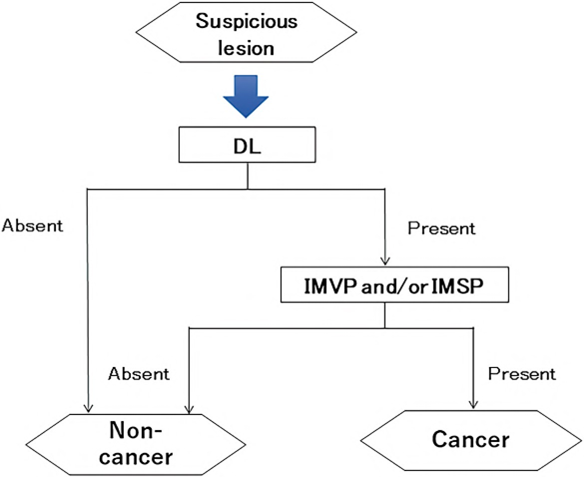

DL is defined as the border between the lesion and non-lesion areas, discernible through an abrupt change in MV and/or MS patterns (. Fig. 2).

The criteria for high-grade dysplasia (HGD)/early cancer (EC) are as follows:

- Presence of an irregular MV pattern with a demarcation line.

- Presence of an irregular MS pattern with a demarcation line.

A target lesion is diagnosed as HGD/EC if it fulfills both or either of the criteria. If it does not meet either of the criteria, it is diagnosed as noncancerous.

The working group members carried out a systematic review of the English literature to determine widely accepted diagnostic systems. Consequently, the best-accepted diagnostic system was proven to be the VS classification system. Based on this system, MESDA-G was constructed using an evidence-based approach (. Figs. 3, 4, 5, and 6) [2]. First, lesions suspicious for EGC should be detected by careful inspection using conventional white-light endoscopy. Subsequently, magnified observations should be performed. Owing to the high sensitivity of the demarcation line [8], if it is absent, the suspicious lesion is diagnosed as noncancerous (. Fig. 4a, b). However, if the demarcation line is present, further assessment is required to determine the presence of an irregular MV or MS pattern. If an irregular MV and/or MS pattern is detected, the suspicious lesion is diagnosed as cancerous (. Fig. 6a, b) [1, 5, 6, 8]. If both the irregular MV and MS patterns are absent, the tumor is diagnosed as noncancerous (. Fig. 5a, b) [1, 5, 6, 8].